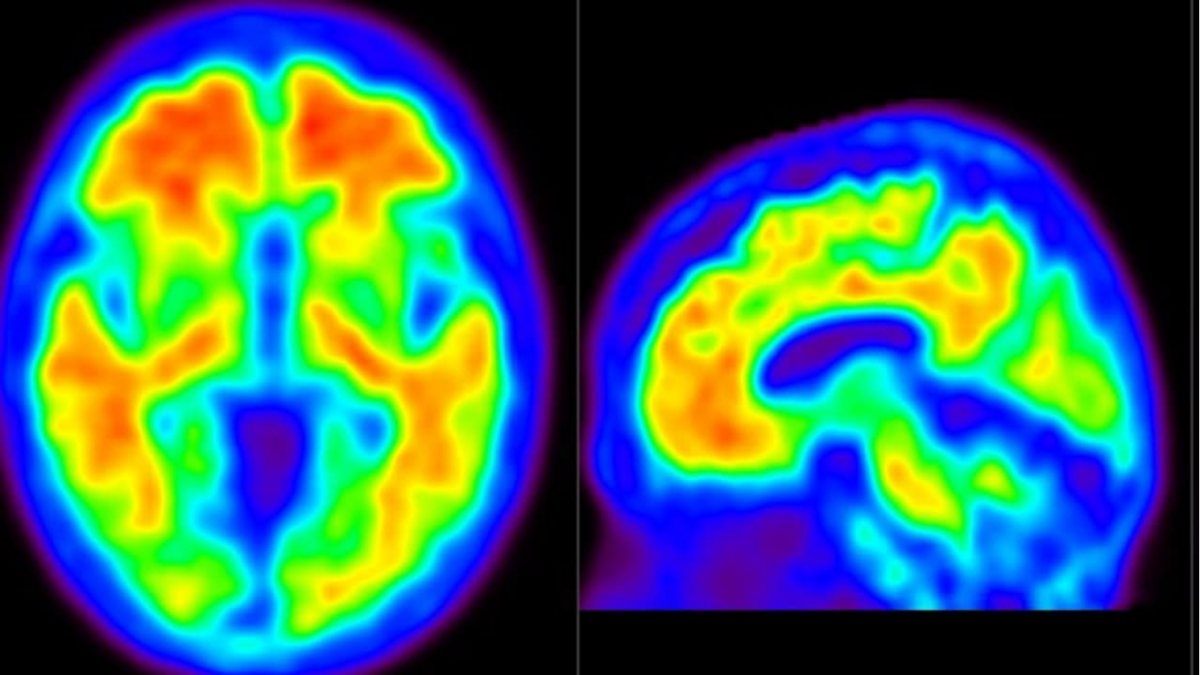

Đây là phương pháp điều trị đầu tiên trong vòng 25 năm nhằm làm chậm suy giảm nhận thức bằng cách loại bỏ mảng bám amyloid trong não, nguyên nhân gây gián đoạn hoạt động của các tế bào thần kinh và dẫn đến suy giảm trí nhớ.